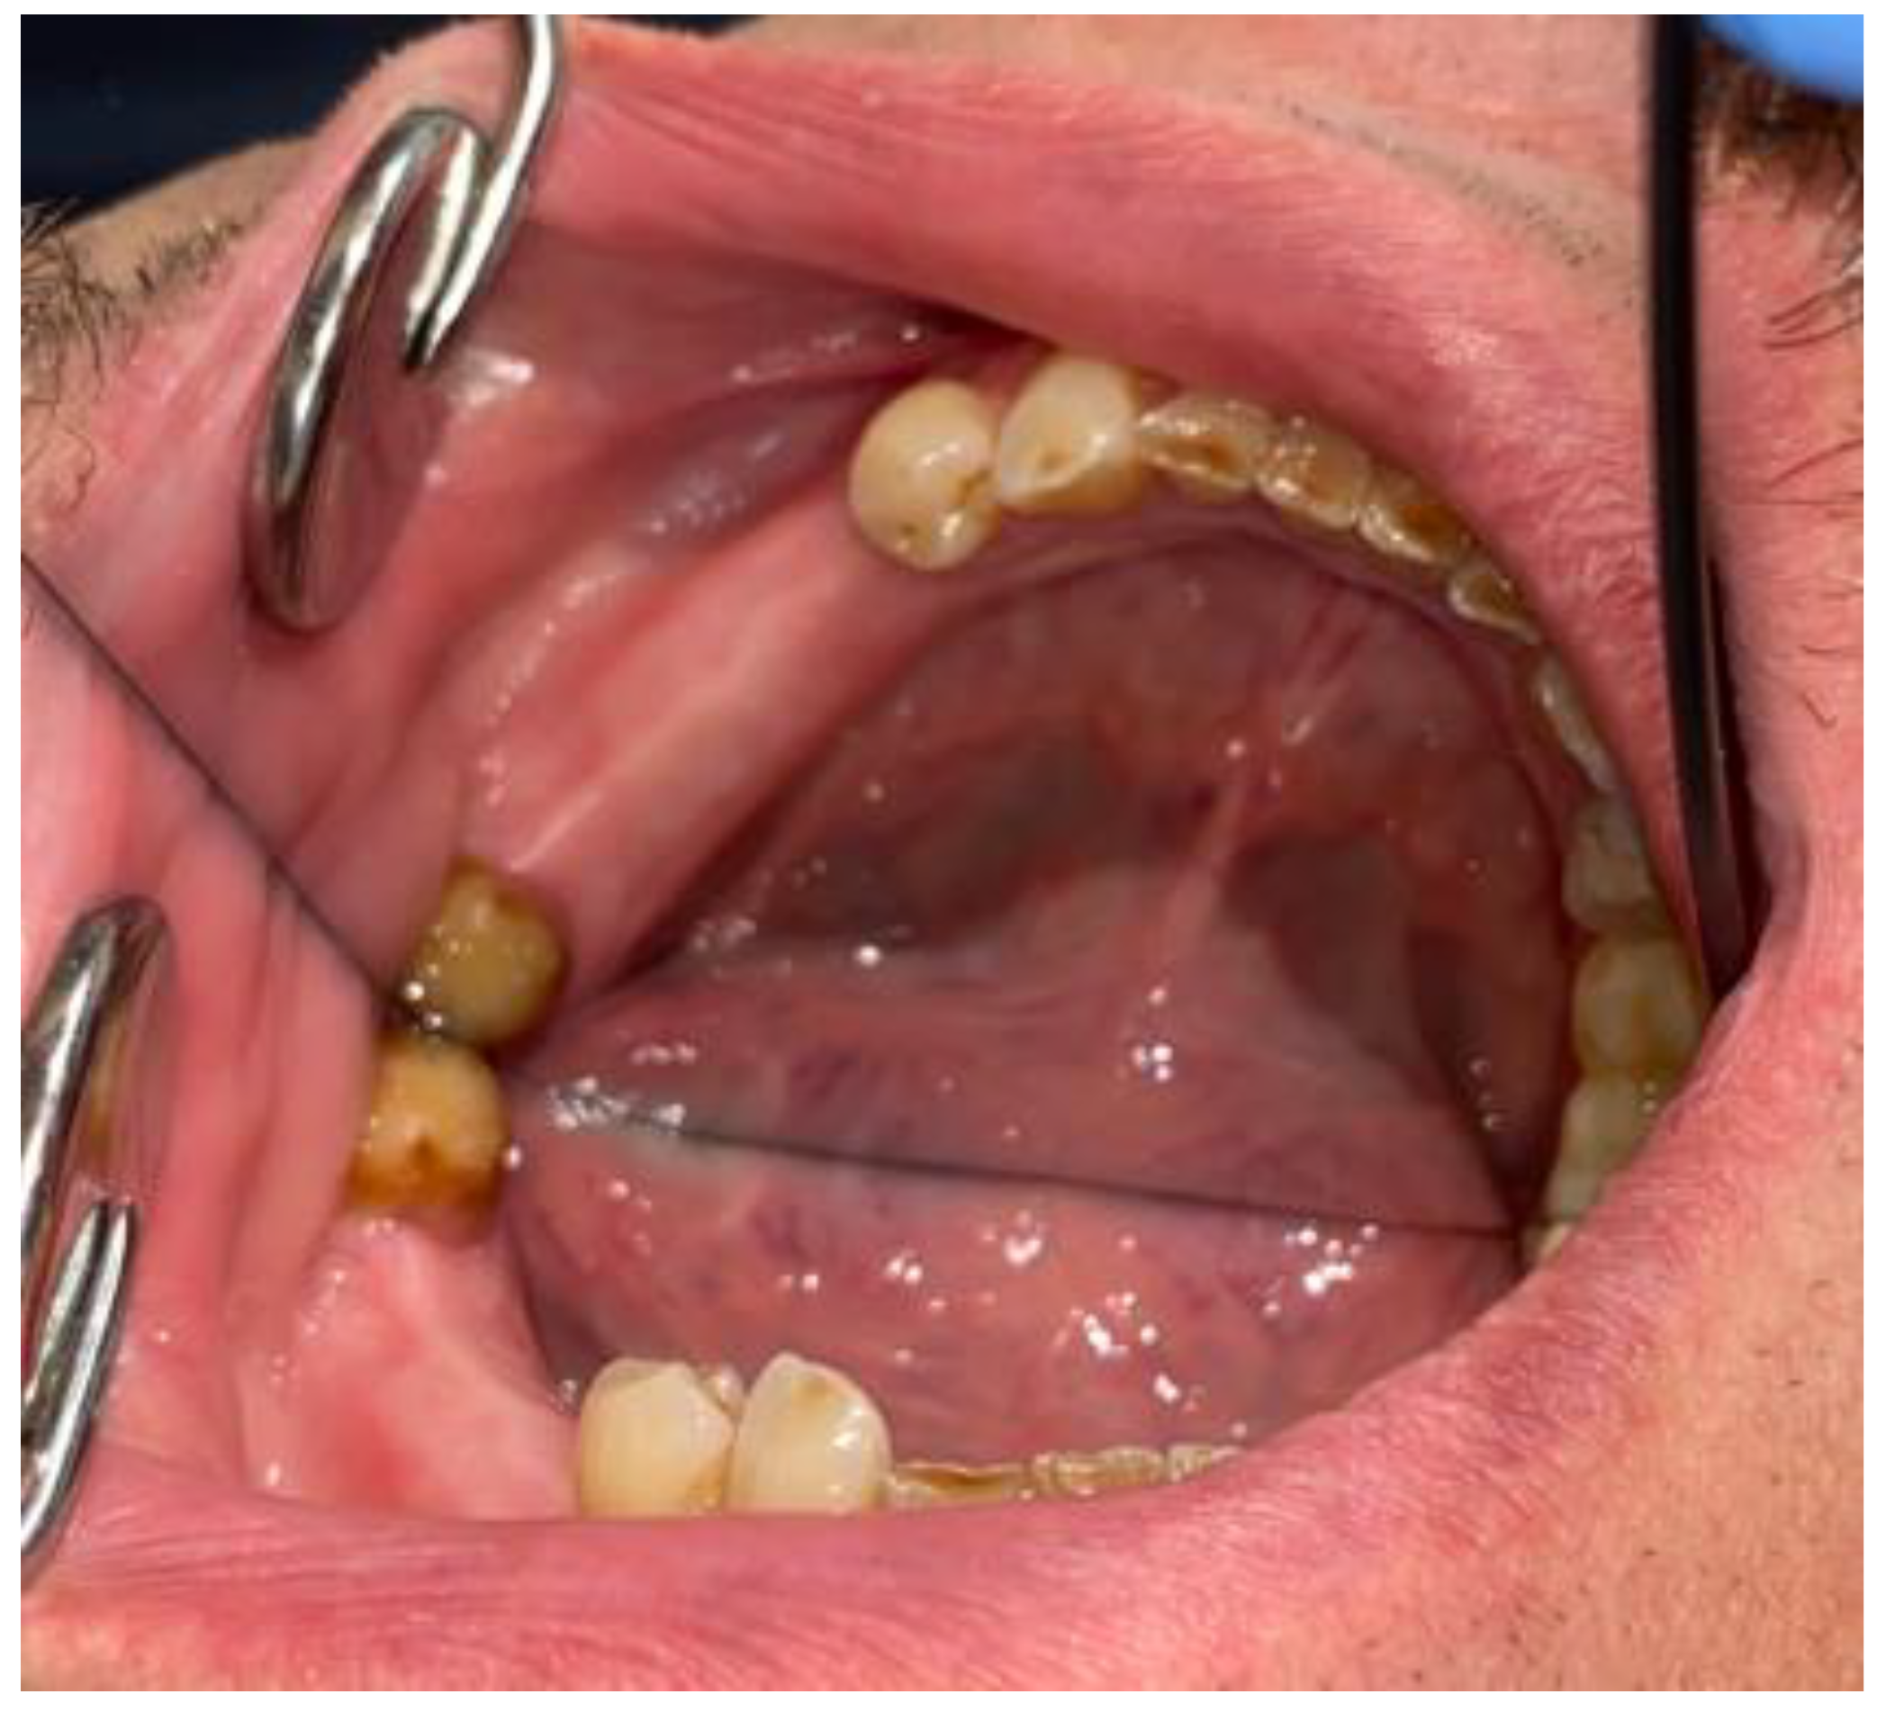

2. Case Description